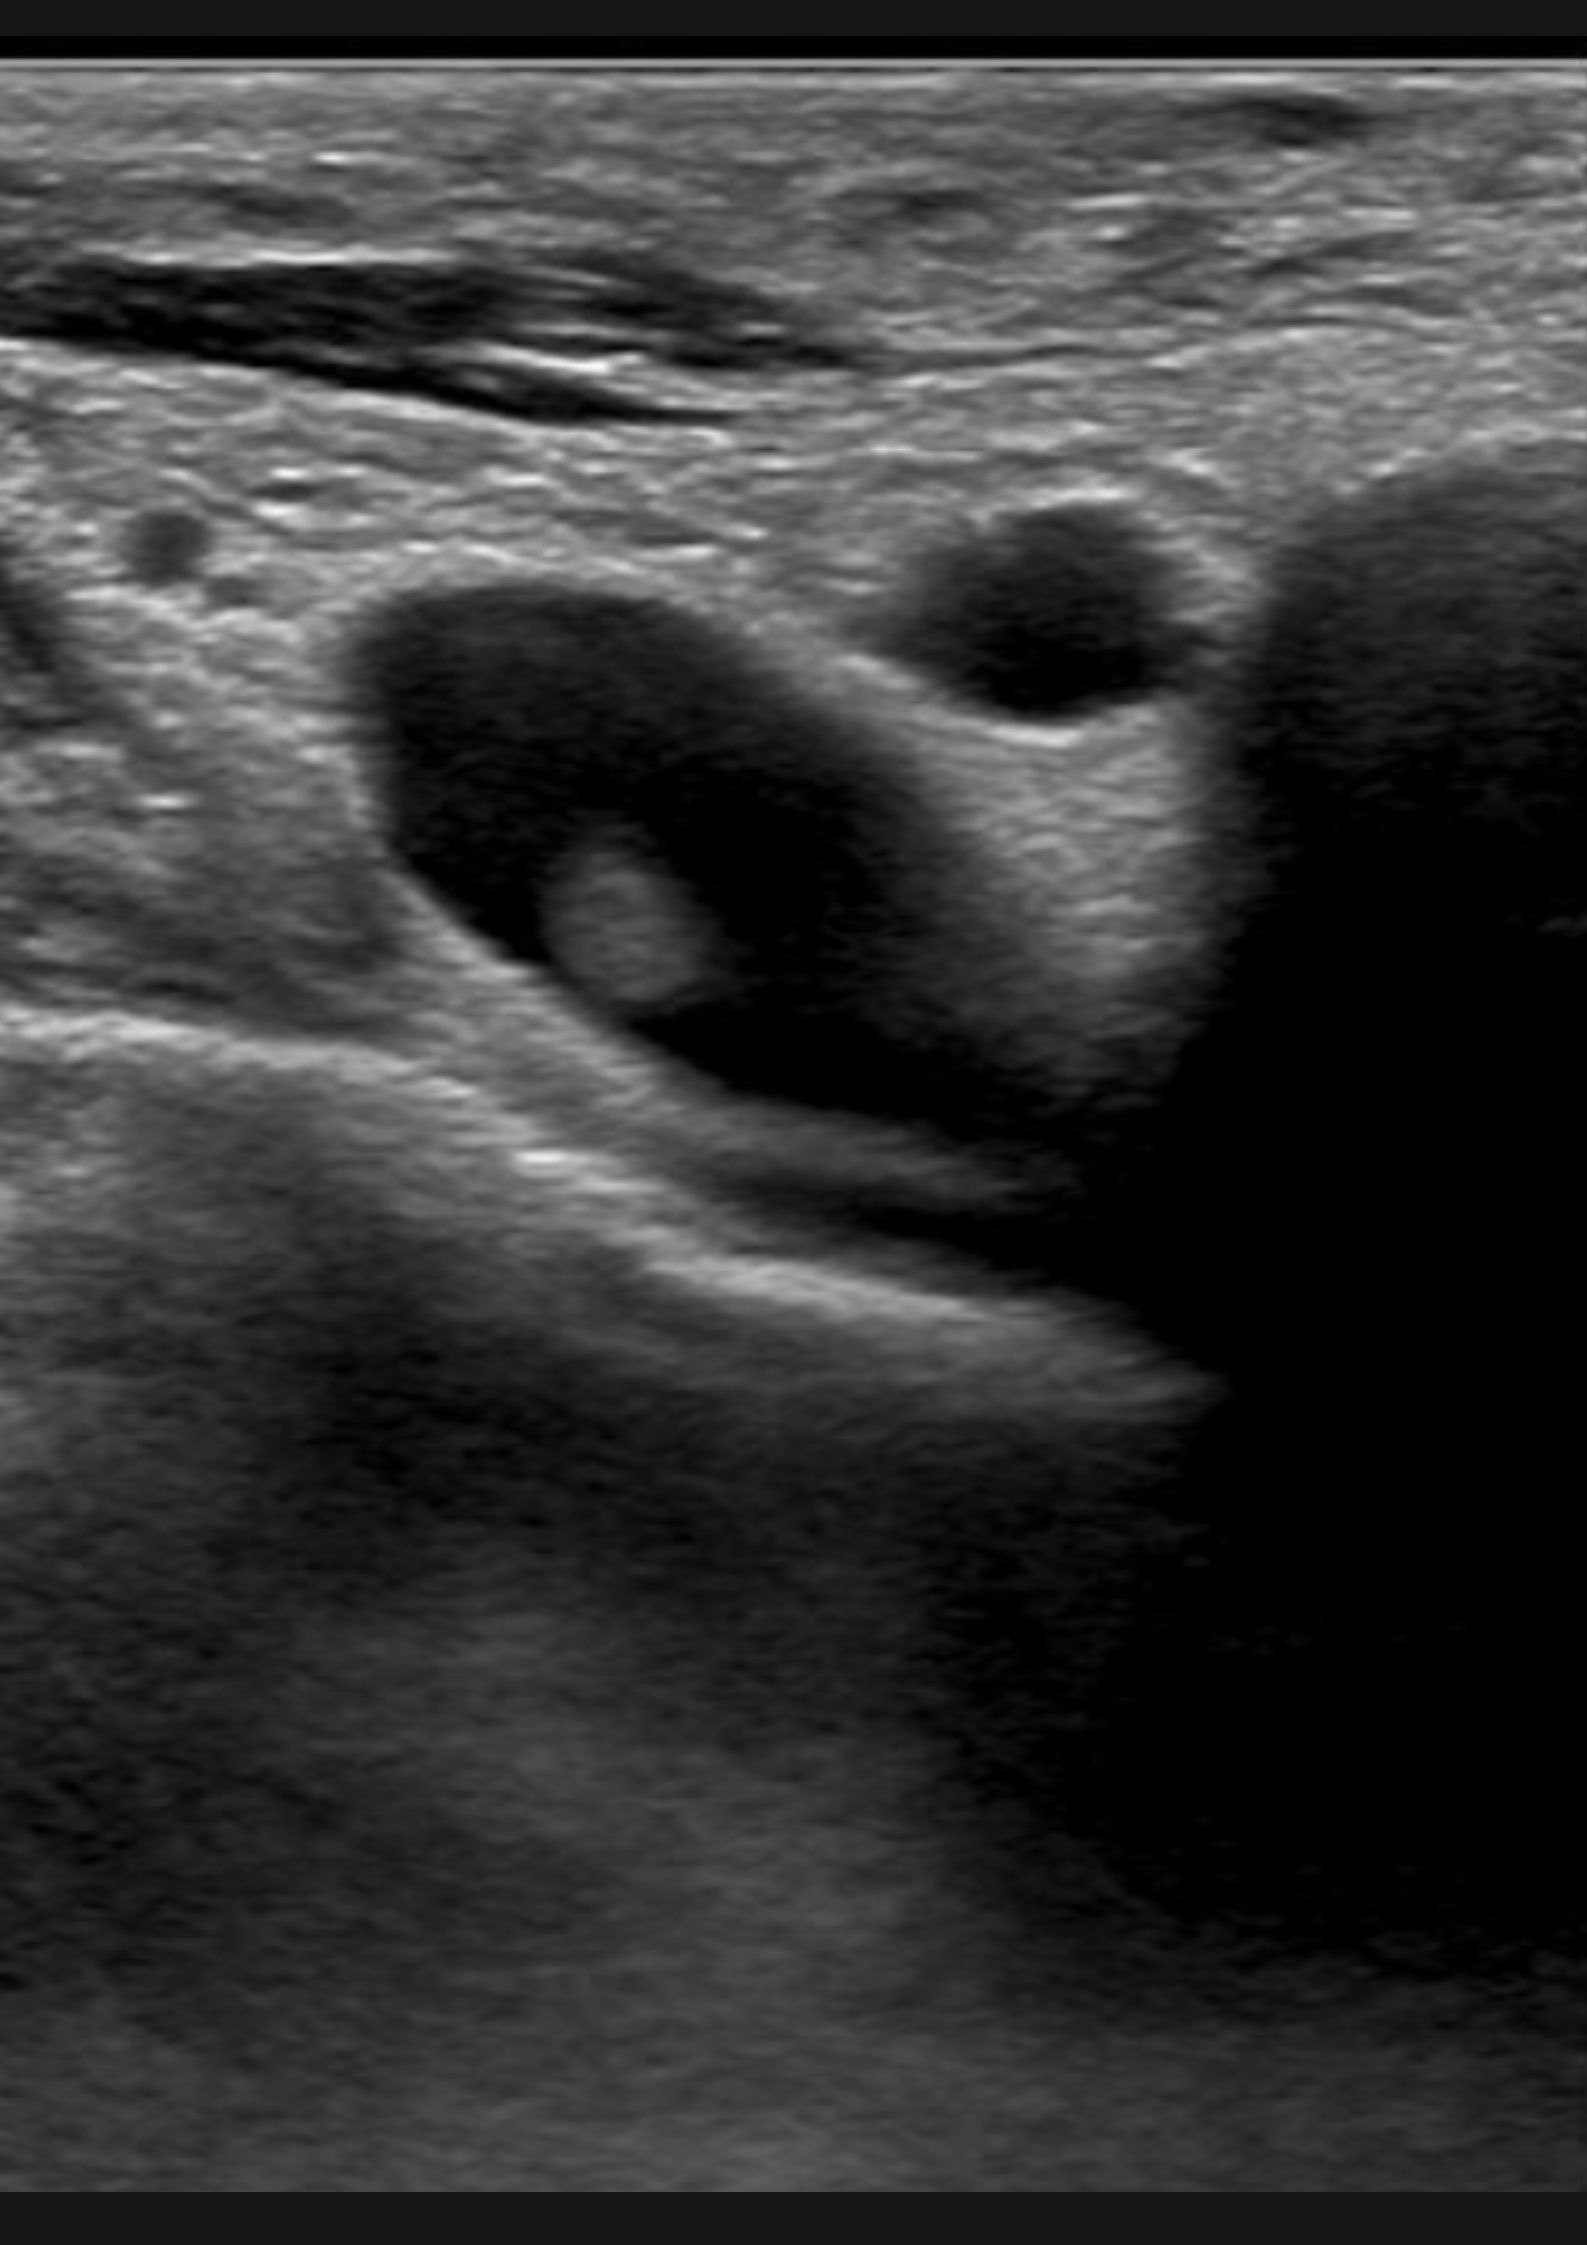

Ante la sospecha de patología muscular sin antecedente traumático, se realiza ecografía.

En la ecografía no apreciamos alteraciones musculares pero observamos dificultad para la compresión de la vena subclavia derecha en extensión.

Trombosis venosa profunda de sublcaiva, innominada, cefálica y yugular derecha.

Se remite a Urgencias del hospital de referencia con hallazgos de coagulación: INR 1.05, fibrinógeno 464, Dímero D 1222; y una ecografía de partes blandas que muestra una trombosis venosa de la vena subclavia derecha y vena innominada, con ligera extensión a la vena yugular derecha y cefálica derecha. Posteriormente, se inicia heparina subcutánea y se realiza fibrinolisis con perfusión de urokinasa. En el estudio de coagulación posterior se determinó una hiperhomocisteinemia y probable síndrome antifosfolípido (Paget-Schroetter).